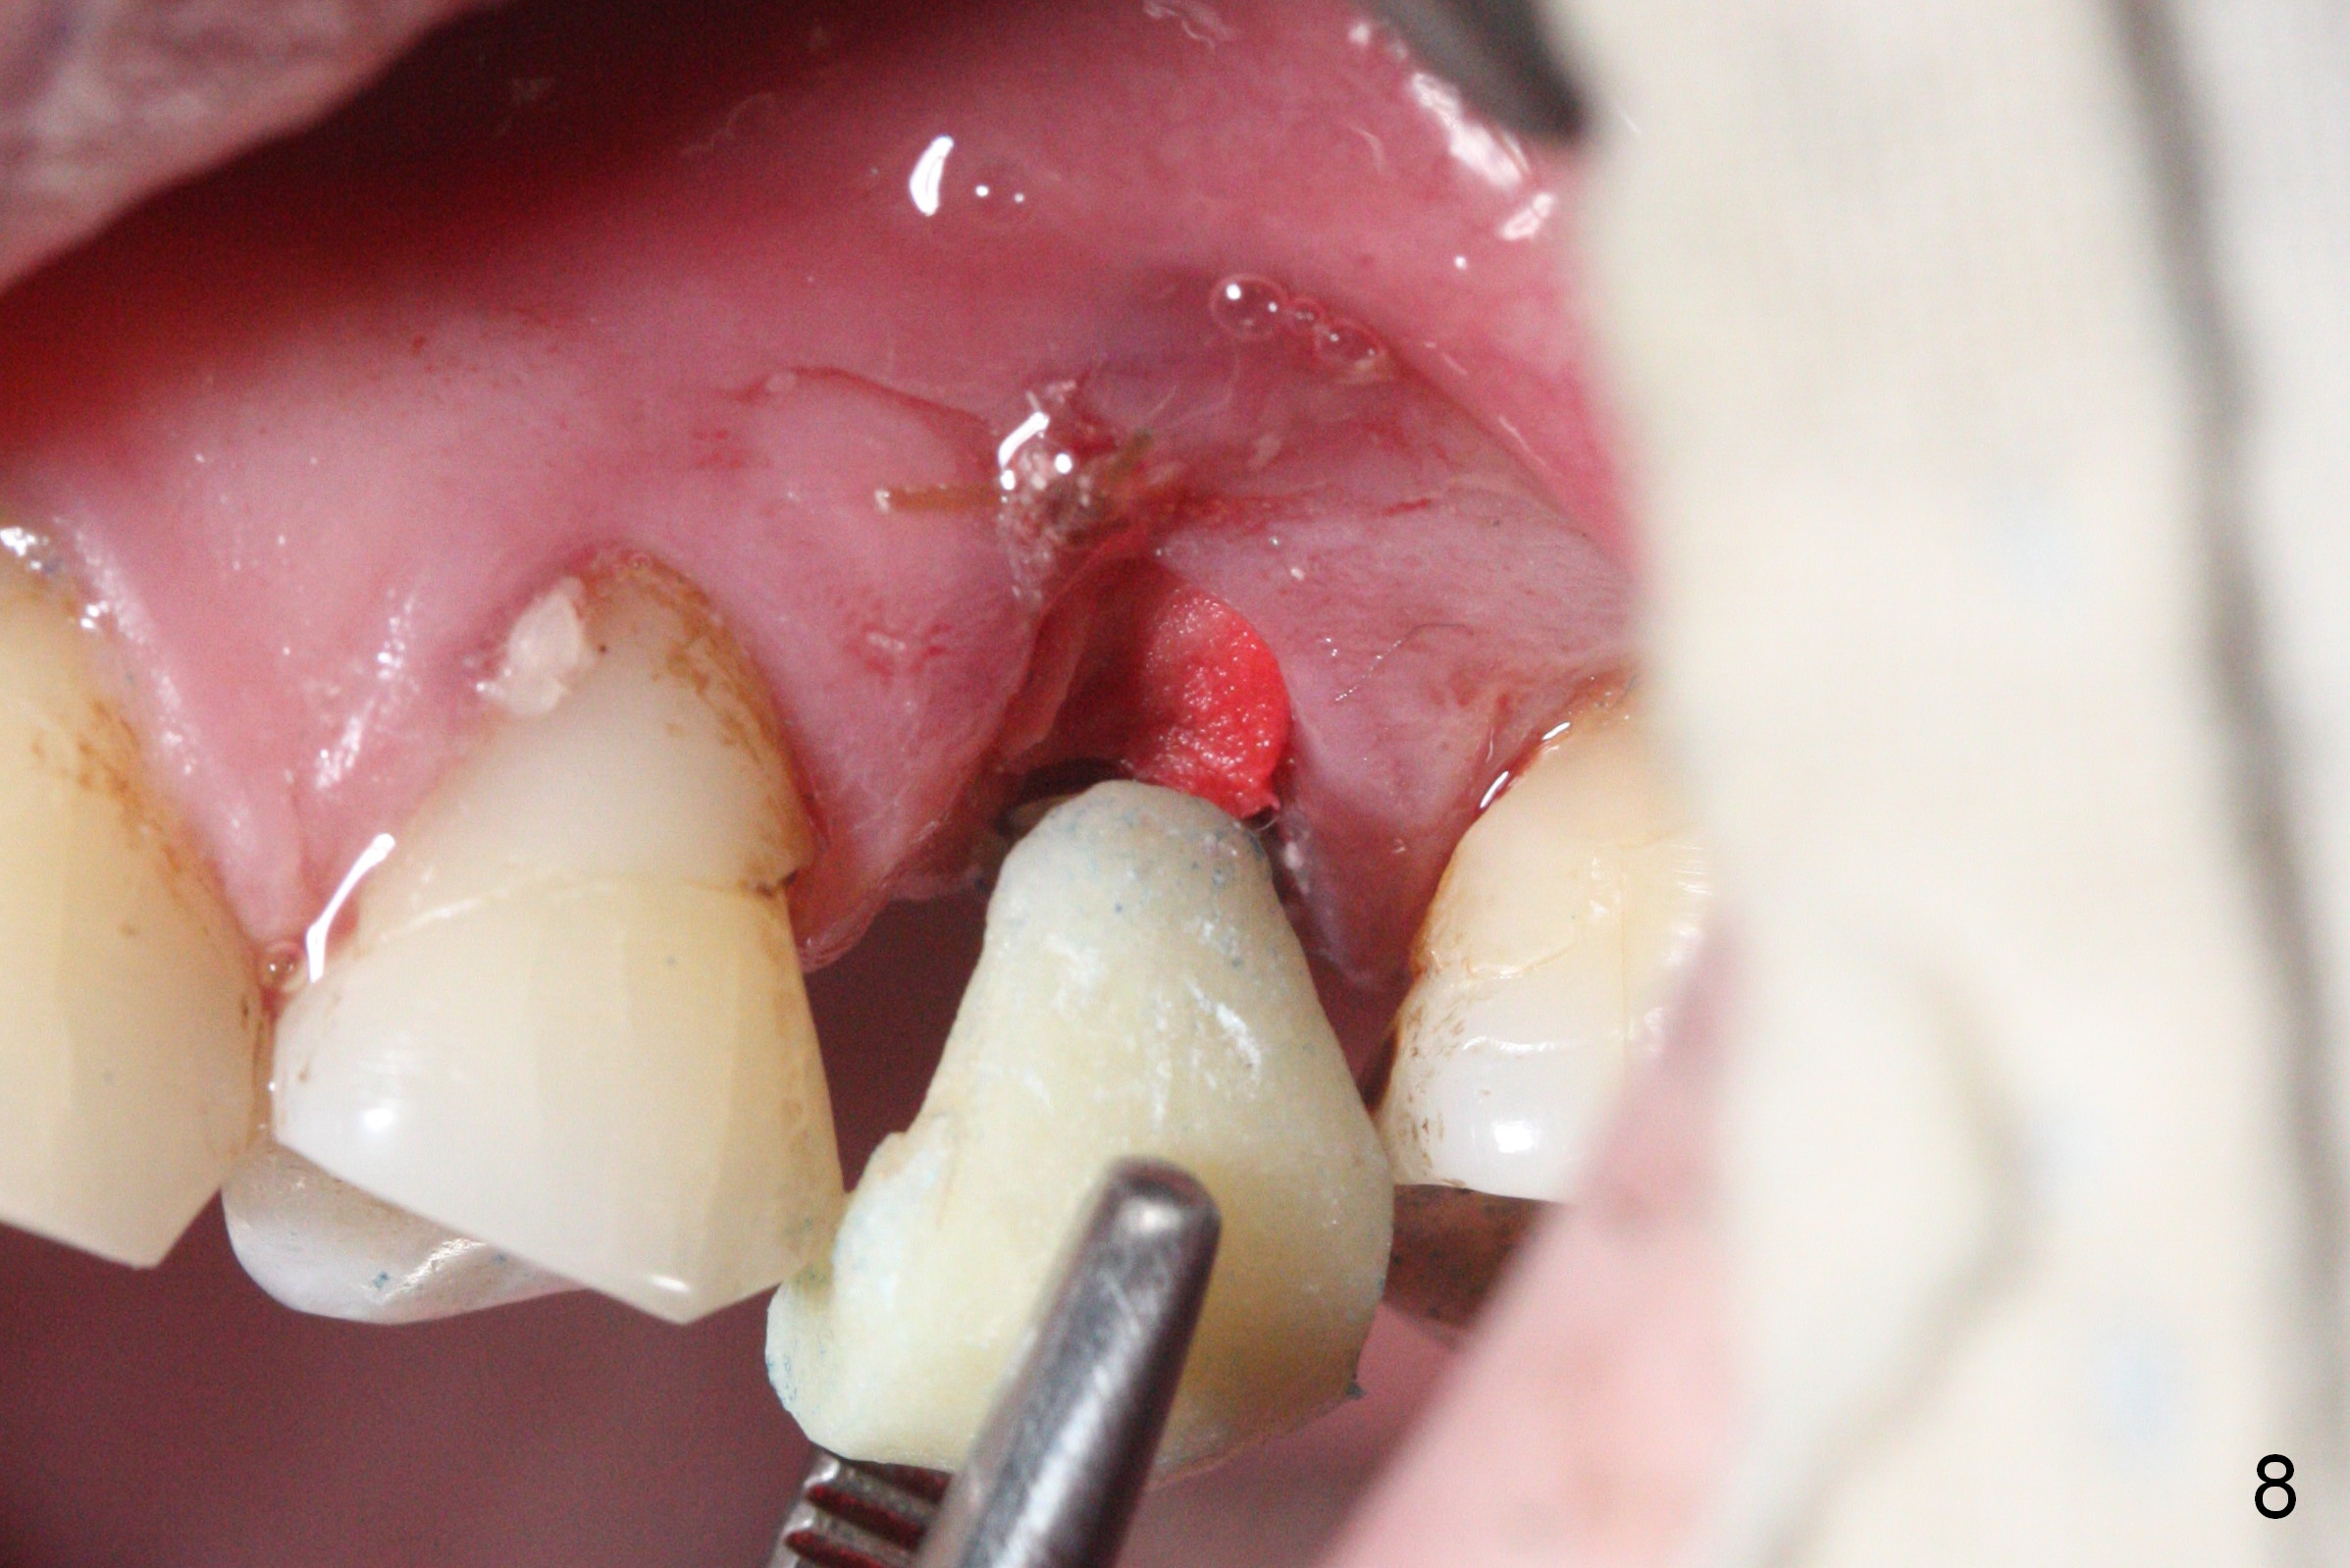

Initial osteotomy depth is 18 mm (Fig.1 green line) with 9 mm in the native bone (red line). The bone density feels to be low. There is at least 2 more mm bone apically (pink line). The depth is increased by 2 mm so that when a 3.8x15 mm implant is placed, there is 10-11 mm implant/bone contact (Fig.2 red line). There is large bony defect (Fig.3 *), which is bone grafted (Fig.4 *). Finally a longer abutment is placed (4.5x5.5(5) in Fig.4 vs. 4.5x4(5) in Fig.2,3). The 5 mm cuff does not look too long buccally (Fig.5) or palatally (Fig.6). To prevent postop buccal gingival overgrowth (2), the buccal margin of an immediate provisional is subgingival (Fig.7-9 *). Bone density between #13 and 14 appears to increase 3 months postop (Fig.10). The implant seems to be equi-crestal (Fig.11 ^). There seems to be more bone growth (i.e., decreasing gap) 6 months postop (Fig.12). Impression is taken. A crown is delivered nearly 7 months postop (08/07/2017). While there is minimal bone loss at #13 and 15 three years and 4 months post cementation, the tooth #14 and 18 are mobile (Fig.13,14).